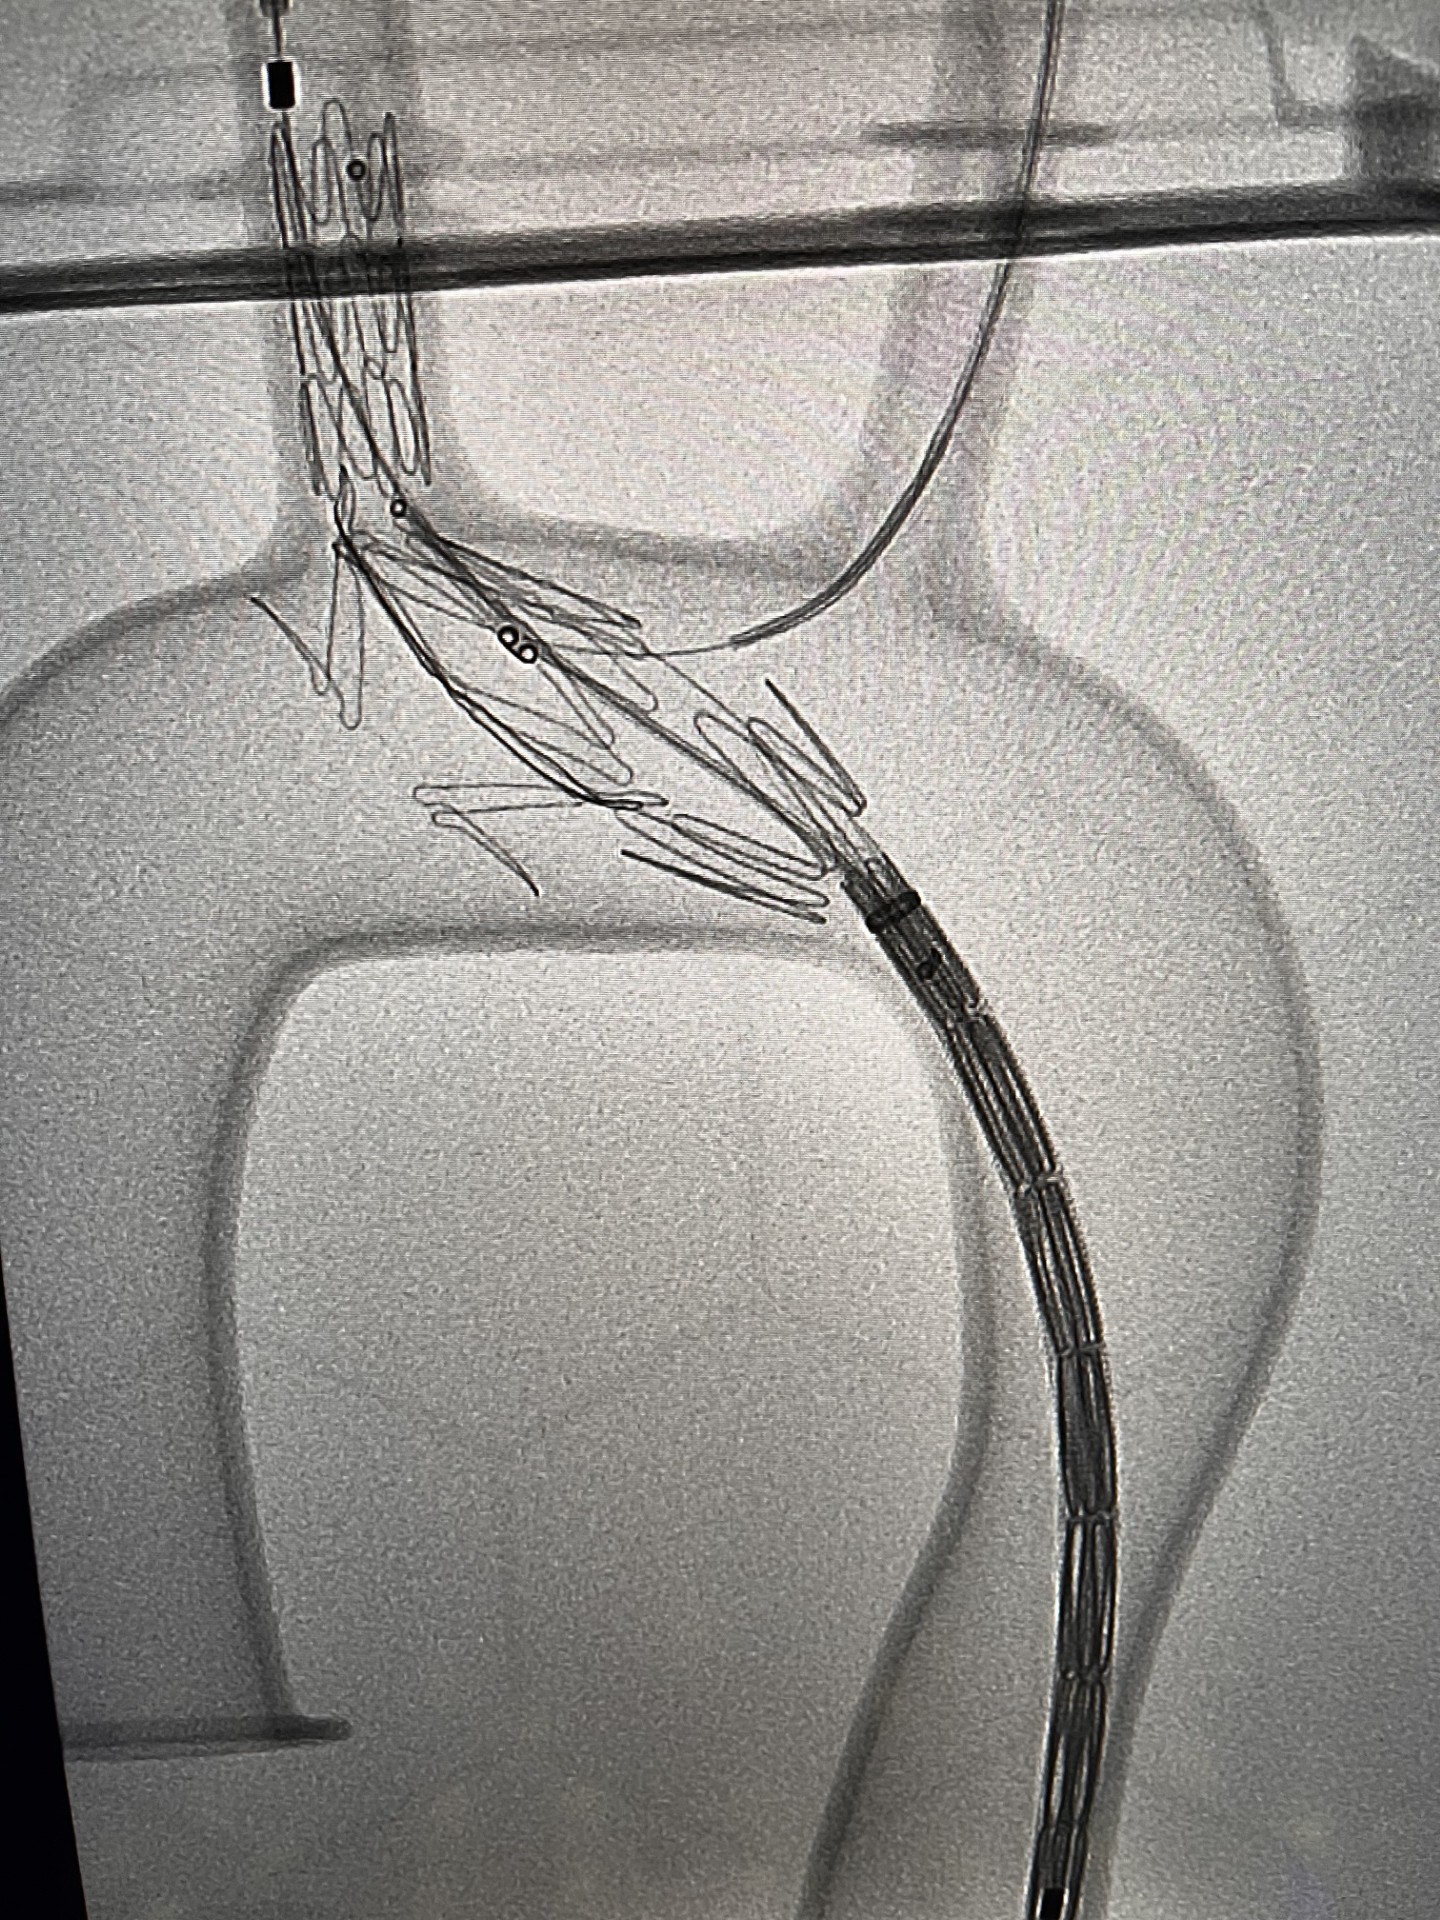

Pod koniec marca br. wykonano pierwszą w województwie pomorskim i trzecią w Polsce operację patologii łuku aorty systemem NEXUS TRE. Dzięki takiej procedurze udało się choremu uniknąć rozległej operacji kardiochirurgicznej z otwarciem klatki piersiowej oraz krążeniem pozaustrojowym.

Zespół chirurgów naczyniowych „Szpitali Pomorskich” rozpoczął w 2023 r. zabiegi endowaskularne w obrębie łuku aorty, dołączając tym samym do elitarnych oddziałów w Polsce. Obecnie ma na koncie liczne, wykonane z powodzeniem zabiegi.

Zabieg był dodatkowo wyjątkowy, gdyż chory obarczony jest niedrożnością obu tętnice szyjnych, odpowiedzialnych za dostarczanie krwi do mózgu. Czas zabiegu oraz zaangażowanie anestezjologa dr Pawła Dutki miał tu decydujące znaczenie — mówi doktor Ryszard Zając, ordynator Oddziału Chirurgii Naczyniowej Szpitala św. Wincentego a Paulo w Gdyni

Udaną operację przeprowadzono ze wsparciem specjalisty klinicznego, doktora Alana Abilio, który przyjechał z Brazylii. Chory bez powikłań udał się w piątej dobie do domu.